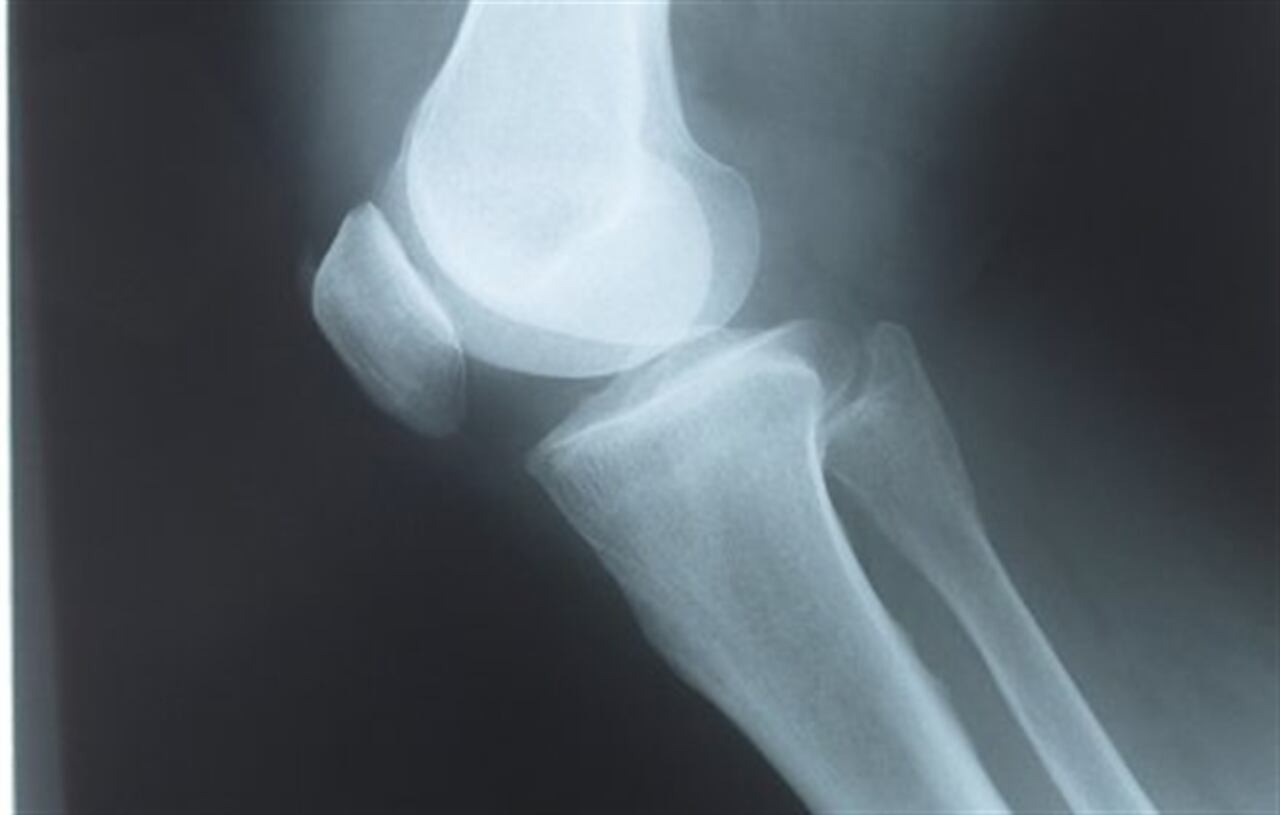

La osteoporosis es una enfermedad del sistema esquelético en la que se presenta una desmineralización de los huesos causando múltiples facturas.

Por otra parte, el informe afirmó que esta es una enfermedad silenciosa. Que no tiene una sintomatología fuerte como dolores para identificarlo. Lo único que lo diagnostica es un examen que identifica la densidad y calidad de los huesos. En la mayoría de los casos cuando la persona presenta fracturas frecuentes se recurre a práctica este examen para evaluar el estado de los huesos.